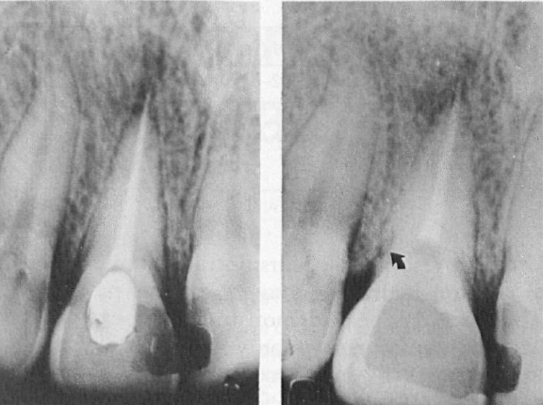

Рис. 3. Клинический случай 3, центральный резец левой верхней челюсти. А. Предоперационная рентгенограмма. Б. Последующая рентгенограмма через 8 лет, на которой отмечается прогрессирующая наружная резорбция корня.

Рис. 4. Клинический случай 4, центральный резец правой верхней челюсти. А. Рентгенограмма до операции. Б. Последующая рентгенограмма через 2 года. Стрелка указывает на область на дистальной поверхности корня, где произошла резорбция и она прекратилась. Периодонтальная связка выглядит нормальной.